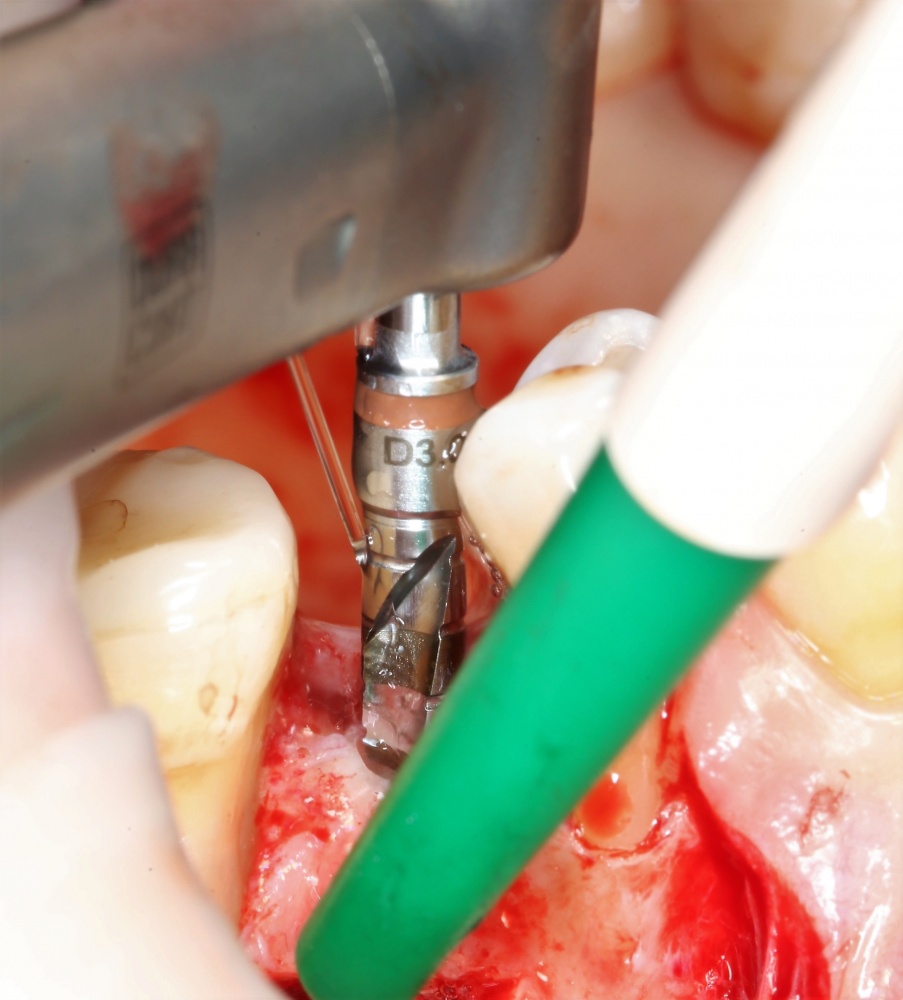

Прежде, чем приступить к аугментации (пластике) лунок зубов, мы подготовили лунки для имплантатов. В таких клинических случаях нет необходимости в использовании шаблона. Вместо этого, мы применяем общепринятые правила позиционирования и соблюдаем рекомендации производителя по хирургическому протоколу:

В процессе ирригации лунки промываются, что позволило нам еще раз подтвердить ранее сделанные выводы. С помощью аналогов имплантатов, входящих в хирургический набор Xive, мы проверили возможность стабилизации имплантатов в будущих лунках. Исходя из правил подбора и позиционирования имплантатов (я очень рекомендую почитать об этом здесь>>) мы остановились на Xive S диаметром 3,4 мм и длиной 13 мм.